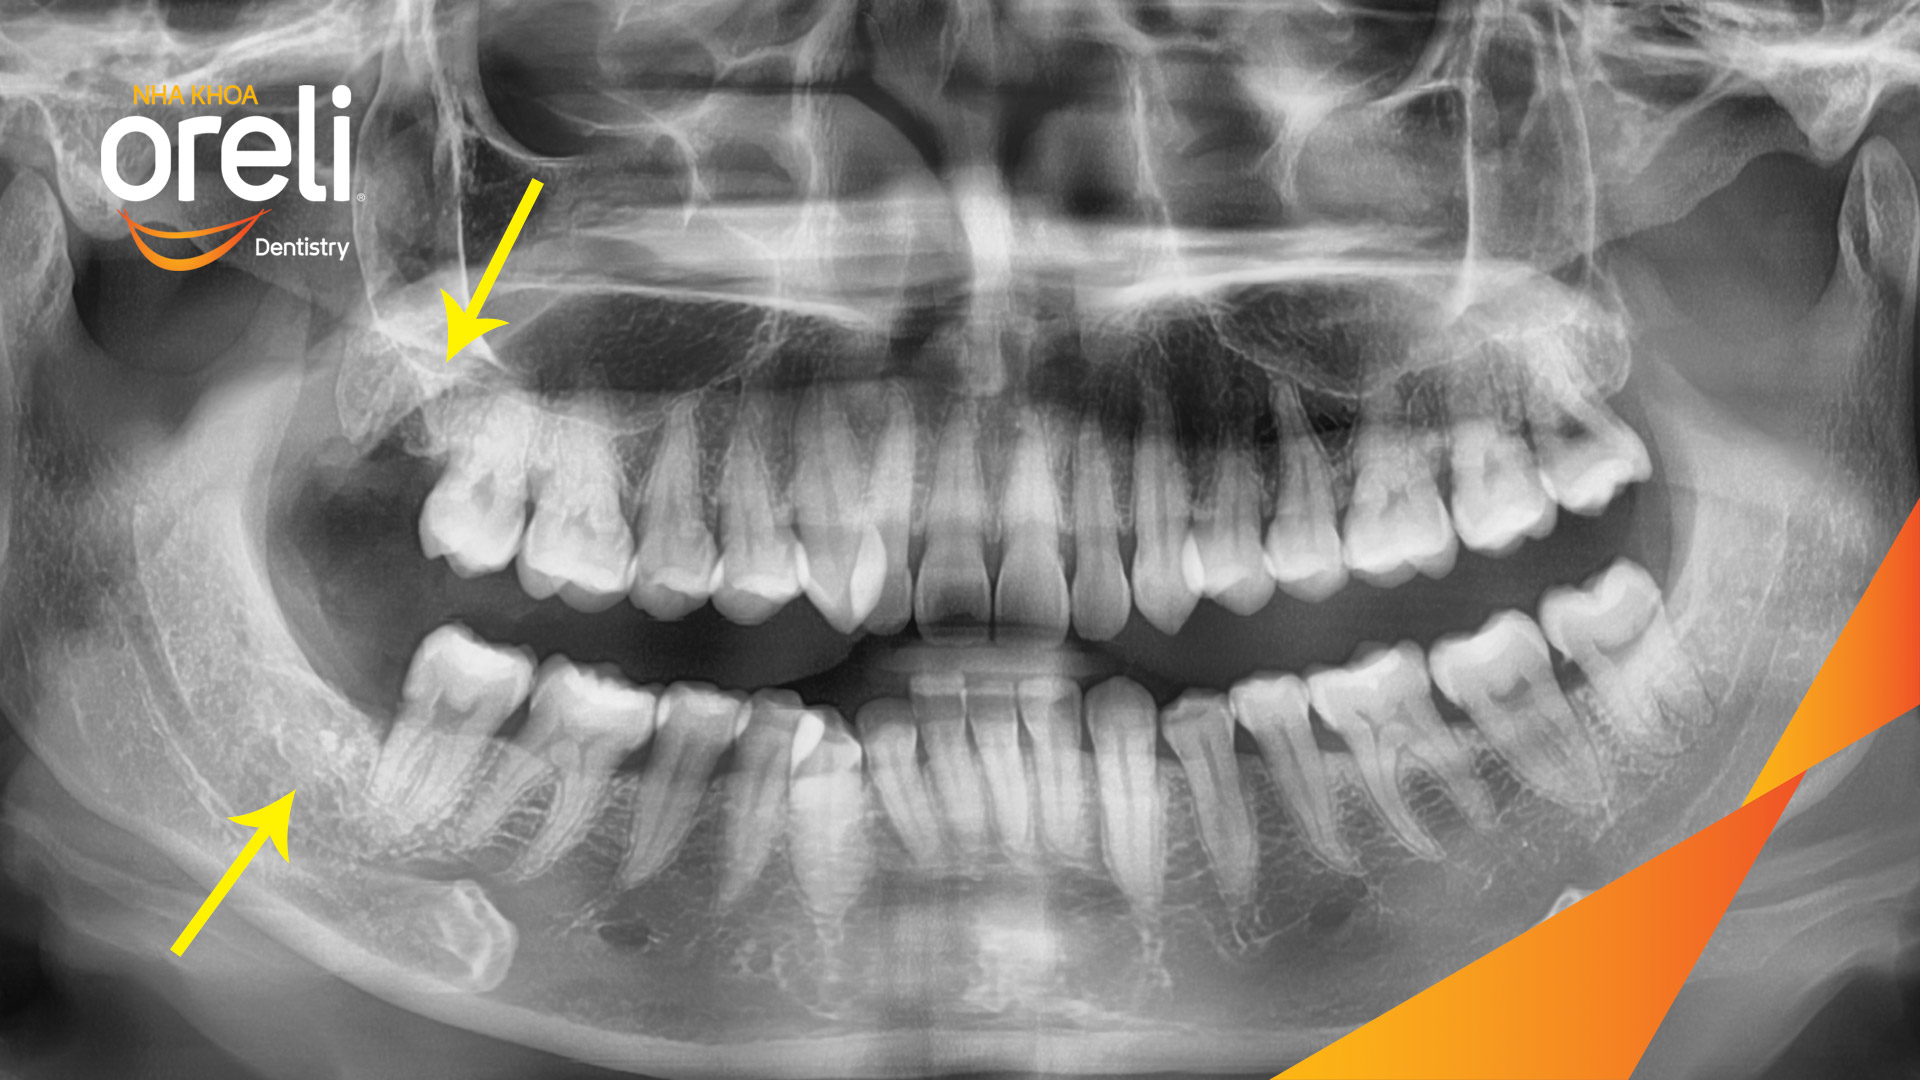

Ca nhổ răng khôn ảnh hưởng răng bên cạnh – Điều trị tại Oreli

Nhổ răng khôn

Mọc lệch

Xem thêm